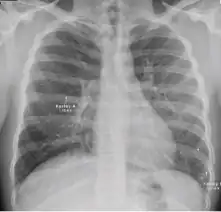

These are films that are completely normal, with no identifiable cardiothoracic or musculoskeletal abnormality.

Normal findings